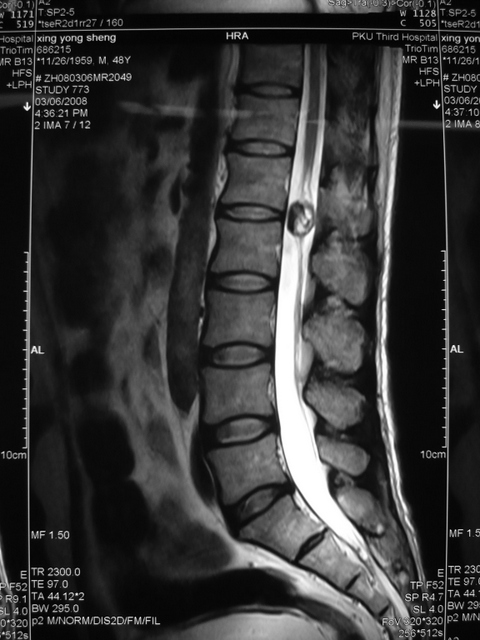

圆锥畸胎瘤